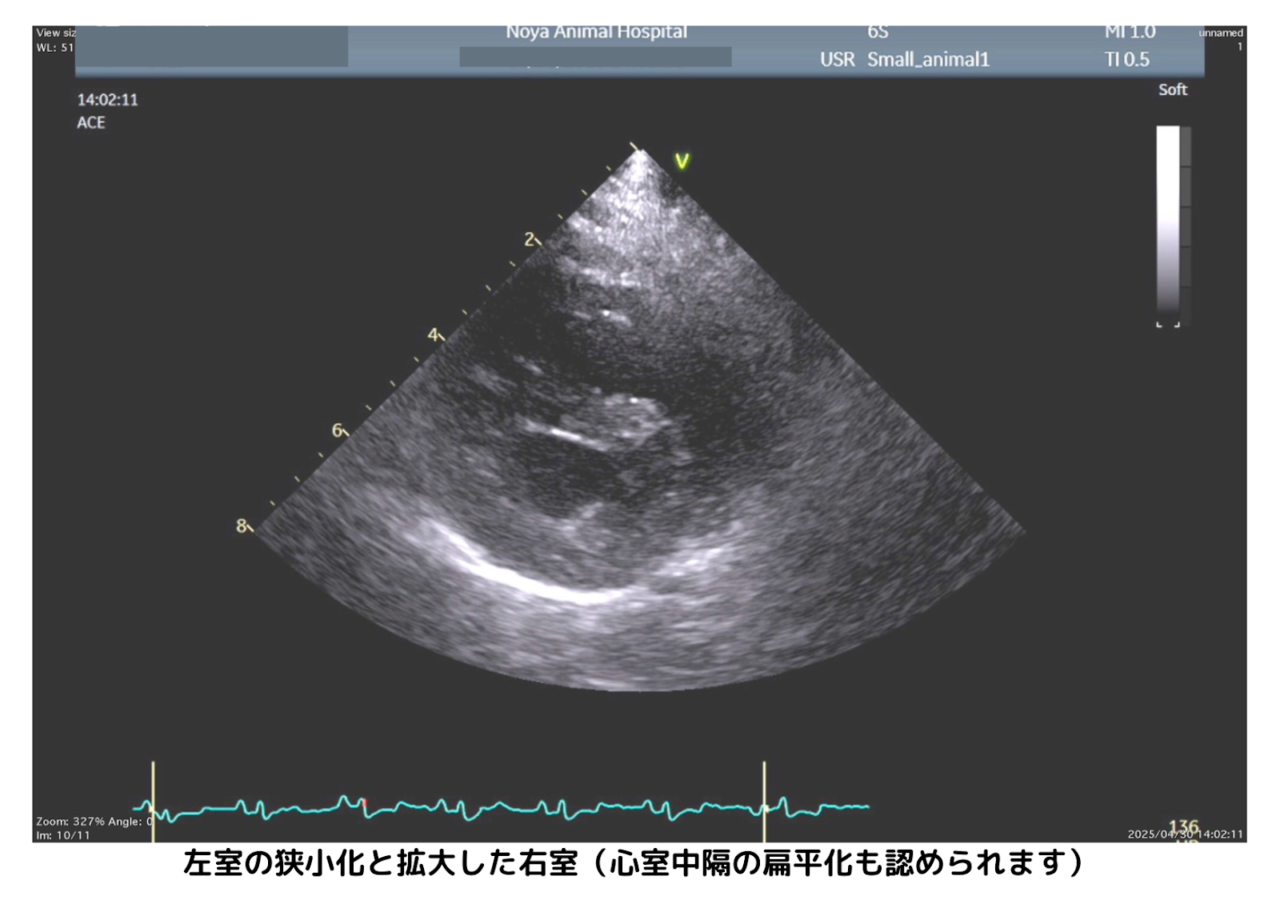

肺高血圧症の犬では、右心室が拡張し、心室中隔が平たく押しつぶされたように見える(扁平化)ことがあります。また、左心室が細く見える(狭小化)所見も、右心系に強い圧力がかかっているサインです。

さらに「三尖弁(さんせんべん)」という右心室と右心房の間にある弁を通る血液の逆流(逆流速度)を測定し、肺動脈の圧力を推定します。

肺高血圧症では、肺の血管に強い圧力がかかることで右心室から血液を送り出す力(=右心室圧)が高くなります。右心室圧は肺動脈圧とほぼ同じため、三尖弁からの逆流速度を測ることで肺動脈の圧力を間接的に知ることができるのです。

実際には肺動脈の圧を直接測るにはカテーテル検査が必要ですが、動物医療では体への負担が大きいため、心エコーで得られる三尖弁逆流の速度(例:4.0m/sなど)から肺動脈圧を間接的に評価するのが一般的です。